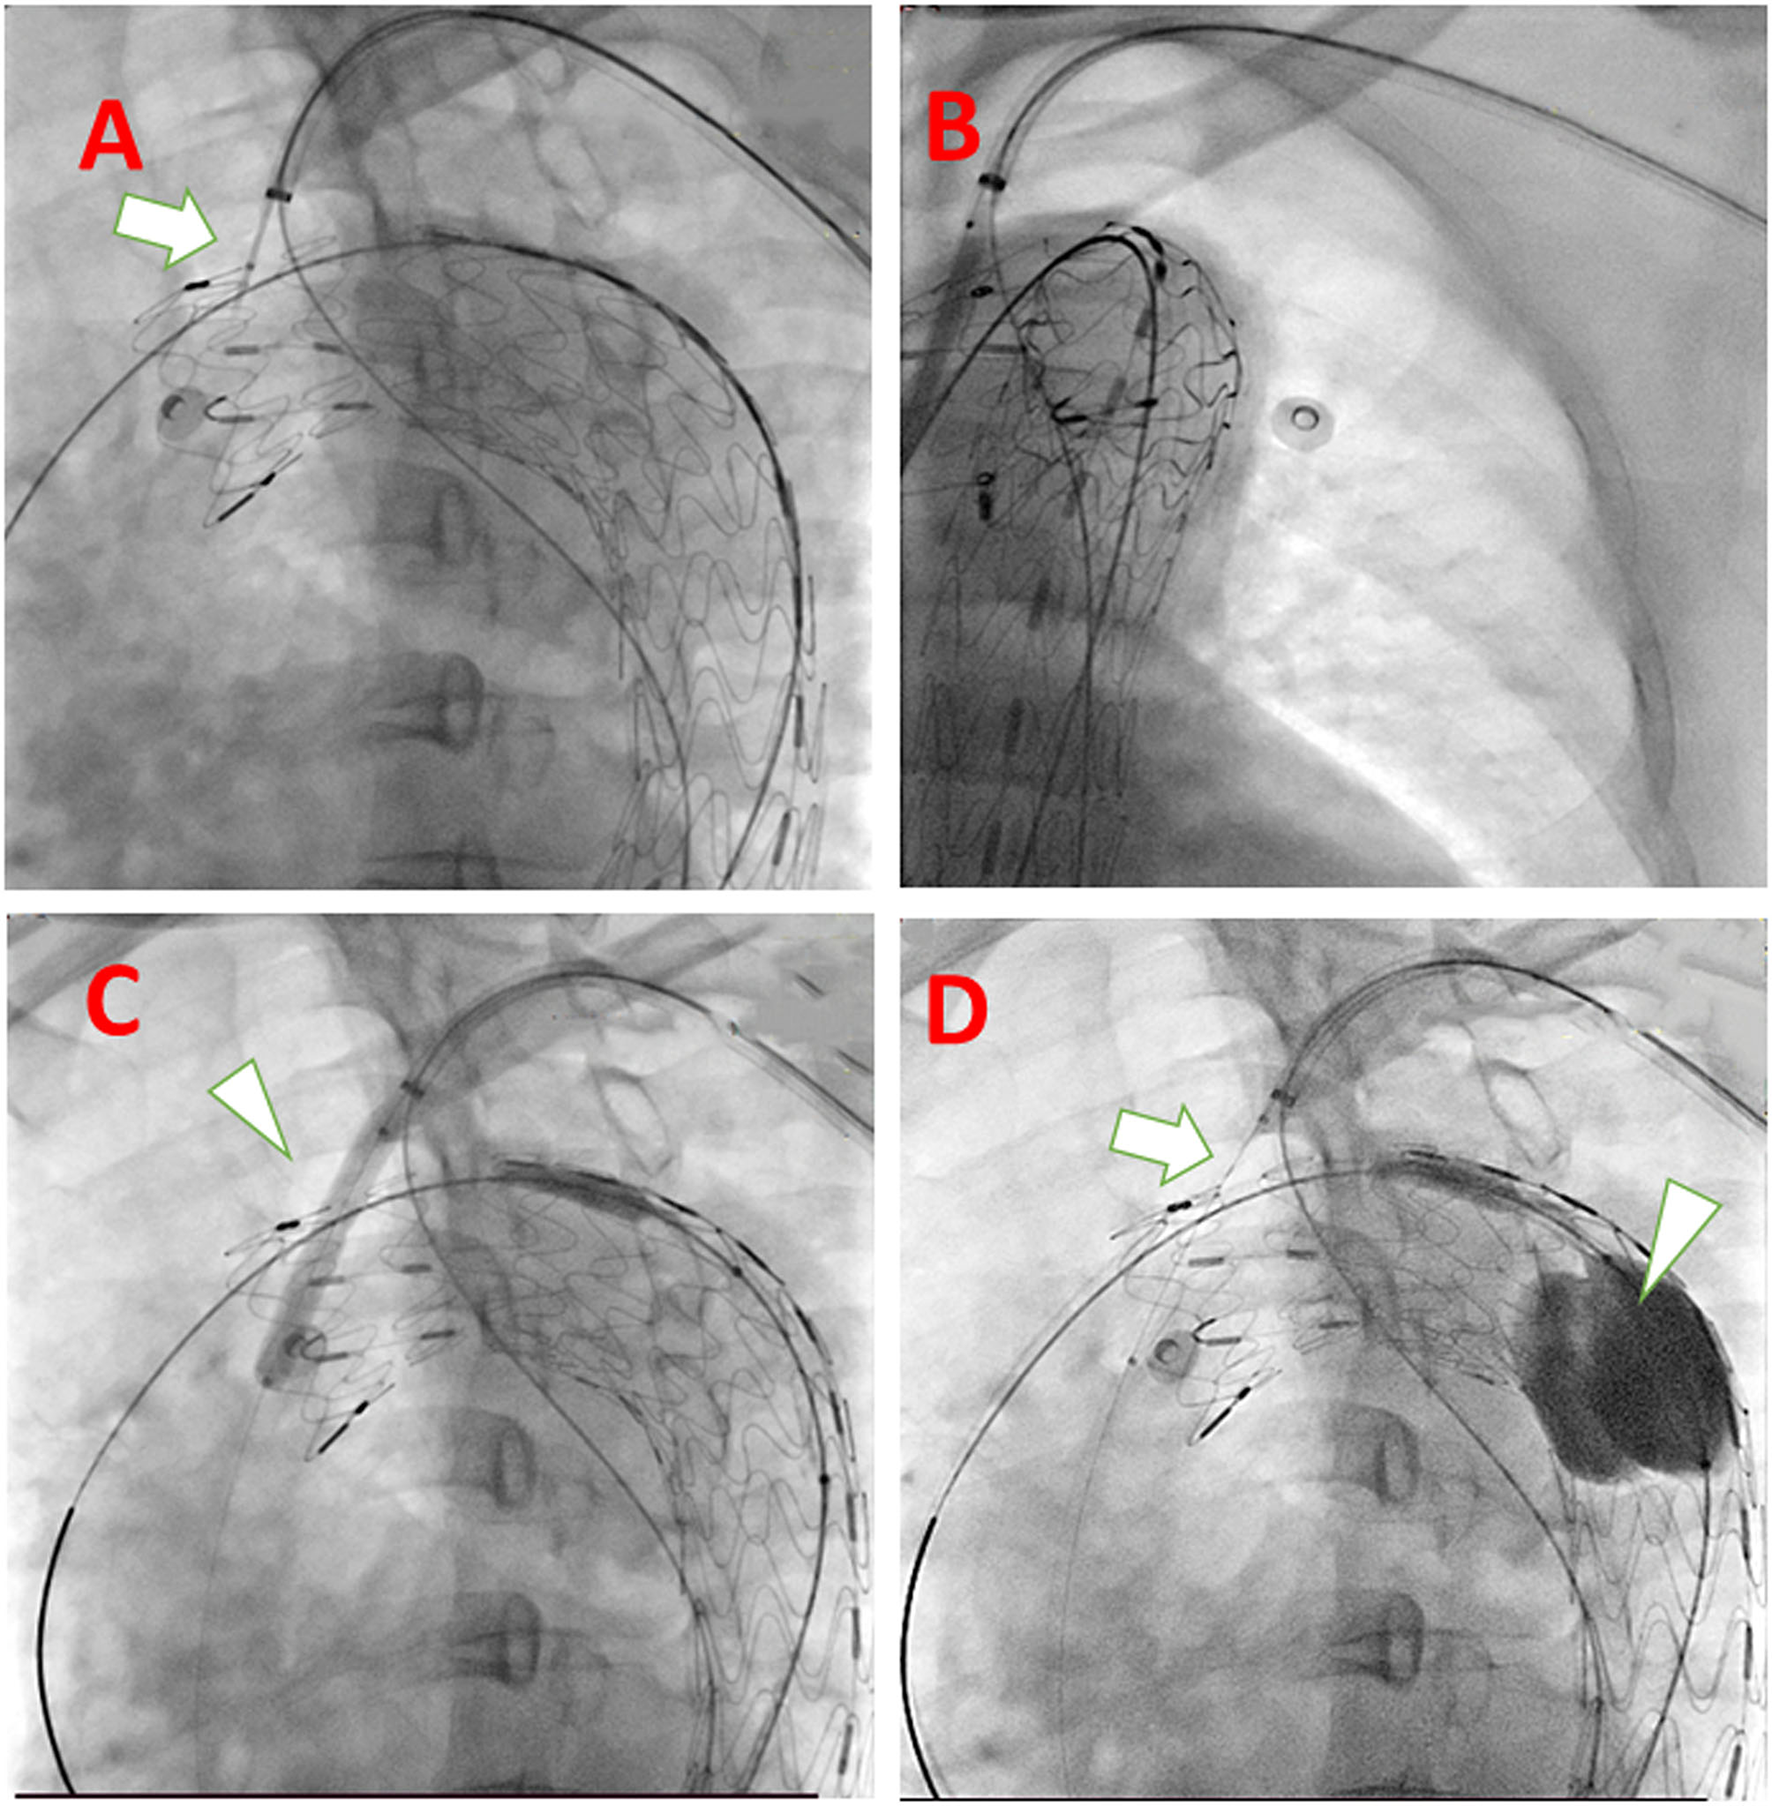

Figure 3

Technical spots mentioned in the system deployment procedure. (A) Puncture needle with descending strengthen wire in the same long sheath when puncturing (white arrow); (B) rotate the tube and make sure the guidewire and expanding balloon into the fenestration is in the lumen of the aortic stent graft; (C) Using larger diameter balloon (white arrowhead) to expand the fenestration; (D) Insert the delivery system of C-skirt stent graft (white arrow) and to prevent migration of aortic stent-graft, a Tri-lobe balloon (white arrowhead) is expanded if necessary.